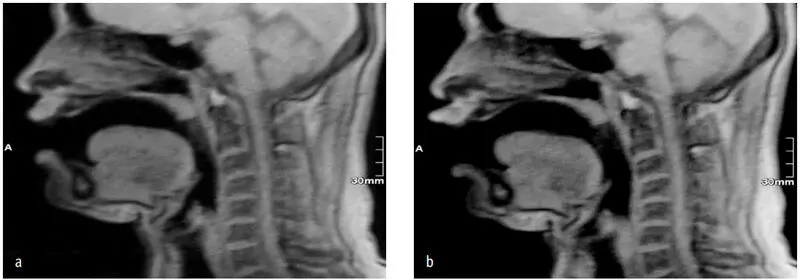

Abb 52 ab Veränderungen der Vokaltraktlänge eines Tenors bei Phonation a im - фото 53

Abb. 52 a/b: Veränderungen der Vokaltraktlänge eines Tenors bei Phonation a) im Falsett, b) in der Bühnenstimme des Tenors; MRT-Aufnahmen